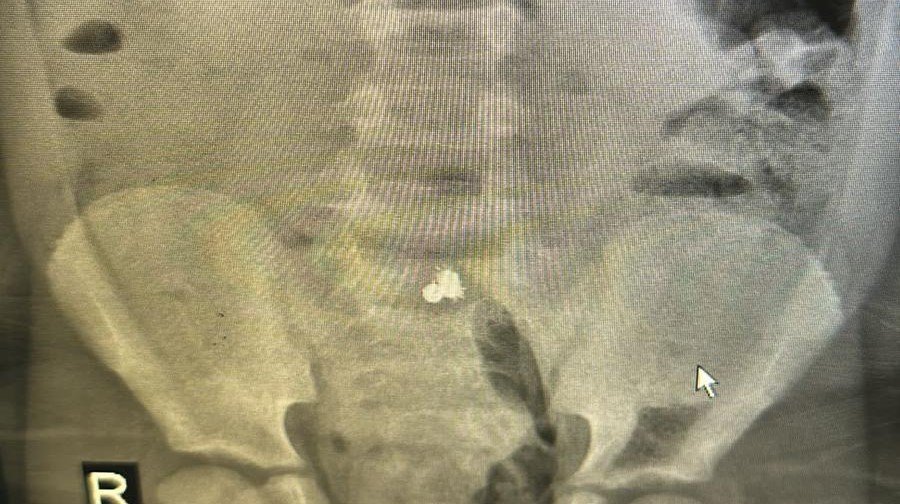

Gündoğdu Mahallesi'nde yaşayan Orhan-Elif Kalay çiftinin ilkokul 1'inci sınıfta öğrenim gören oğulları Miraç, okulda oyun oynarken mıknatıslı bilyeleri yuttu. Şiddetli karın ağrısı ve kusma şikayetiyle ailesi tarafından Recep Tayyip Erdoğan Üniversitesi Eğitim ve Araştırma Hastanesi'ne götürülen Miraç'ın çekilen röntgen filminde, bağırsağında 3 küçük mıknatıslı bilye tespit edildi.

Yapışık halde bilyelerin bağırsağını deldiği ortaya çıkan Miraç, ameliyata alındı. Yaklaşık 2 saatlik operasyonla bilyeler alındı. Küçük Miraç, gözlem altına alındığı serviste tamamlanacak bağırsak tedavisi sonrası taburcu edilecek.